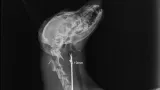

Maleni pas mješanac pogođen je dijabolom u vrat, a budući da je metak ostao smješten na nezgodnom mjestu blizu kralježnice, veterinar Mate Karaula iz Daruvara koji liječi Lenu, odustao je od vađenja metka zbog daljnjeg rizika po kujicu.

Prema nalazu veterinara dr. Mate Karaule, rendgenska snimka pokazala je da se metak, točnije dijabola, nalazi u području između atlasa i aksisa – dijela vratne kralježnice.

- Veličina projektila procijenjena je na 6,10 do 5,16 milimetara, a zbog dubine položaja i blizine kralježnice procijenjeno je da bi pokušaj vađenja mogao izazvati ozbiljne komplikacije. Zbog toga se odustalo od kirurškog vađenja metka.

Pas je primio injekcijsku sedaciju, obavljene su dvije rendgenske snimke i kirurška obrada rane, kazao nam je dr. Karaula.